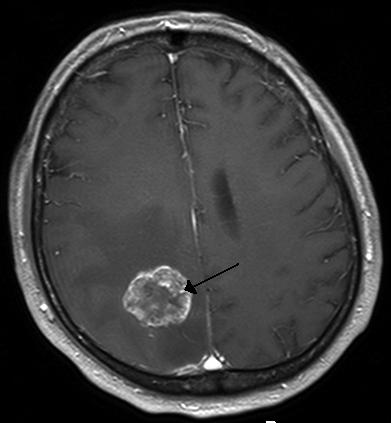

Brain Tumor

Figure 4. A metastatic tumor in the cerebral hemisphere from lung cancer, shown on magnetic resonance imaging.